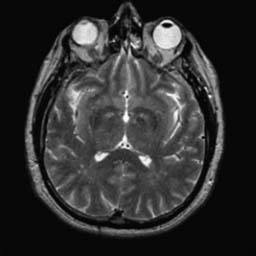

To demonstrate the effectiveness and efficiency of the proposed image fusion method , we conduct a set of comparative experiments on three image datasets. The first is composed by 8 pairs of multi-modal medical images and the second one contains 15 pairs of multi-focus gray or color natural images. These two datasets are often used in many related papers and some examples are shown in Figure 3(a) and Figure 3(b). The third one is a new multi-focus cervical cell image dataset collected by ourselves, which consists of 15 groups of color images and each group contains a series of multi-focus cervix cell images with size of or , etc. Some source examples are shown in Figure 3(c). Our source code implemented in C++ along with the new multi-focus cervical cell image dataset is available online.

We first evaluate the performance of the proposed method under varying total number of octaves and number of layers sampled per octave. The fused images of a pair of multi-modal medical images with different and are shown in Figure 4. In this example, on the one hand, when only 1 or 2 octaves are involved in constructing the DoG pyramid, the fused images fail to keep the integrity information of large size objects (e.g. eyeballs), while by increasing the value of , the integrity information of eyeballs is preserved. On the other hand, although not as significant as the increase of octave numbers , the fused image can contain more details by the increase of layer numbers . The corresponding objective quality metrics are shown in Figure 5. As shown in Figure 5(a), most of the metric values are improved as the number of octaves increases with the fixed layer numbers 3 in the global tendency and each of them tends to be stable when the number of octaves is 5. To get a relatively good quality from Figure 5(b), we can notice that some of the metric values can get a good performance when the number of layers is 3, such as the MI, SSIM, QI and VIF, though there are only a little change of all the metric values by increasing the number of layers with the fixed octave numbers 5. Because it will result in more computation burden with the increase of the value and , and for different kinds of source images, there are different performance with the diverse parameter settings. To get a trade-off between them in our experiments, we set for the multi-modal dataset, for the natural datasets and for the multi-focus cell dataset, respectively.

Figure 6 shows the fused images obtained by different methods with the multi-modal source images shown in Figure 3(a). As shown in these figures, the proposed method can produce images which preserve the complementary information of different source images well. Moreover, due to the scale-invariant structure saliency selection, our method can keep the integrity information of large size objects and the visual details simultaneously. Although the fused image generated by other methods can also capture the details to some extent, all of them fail to keep the integrity information of large size objects such as the eyeballs. Furthermore, from Figure 6(k)-6(t), the DTCWT, GFF, IM and NSCT methods may decrease the brightness and contrast while the proposed method can preserve these features and details without producing visible artifacts and brightness distortions.